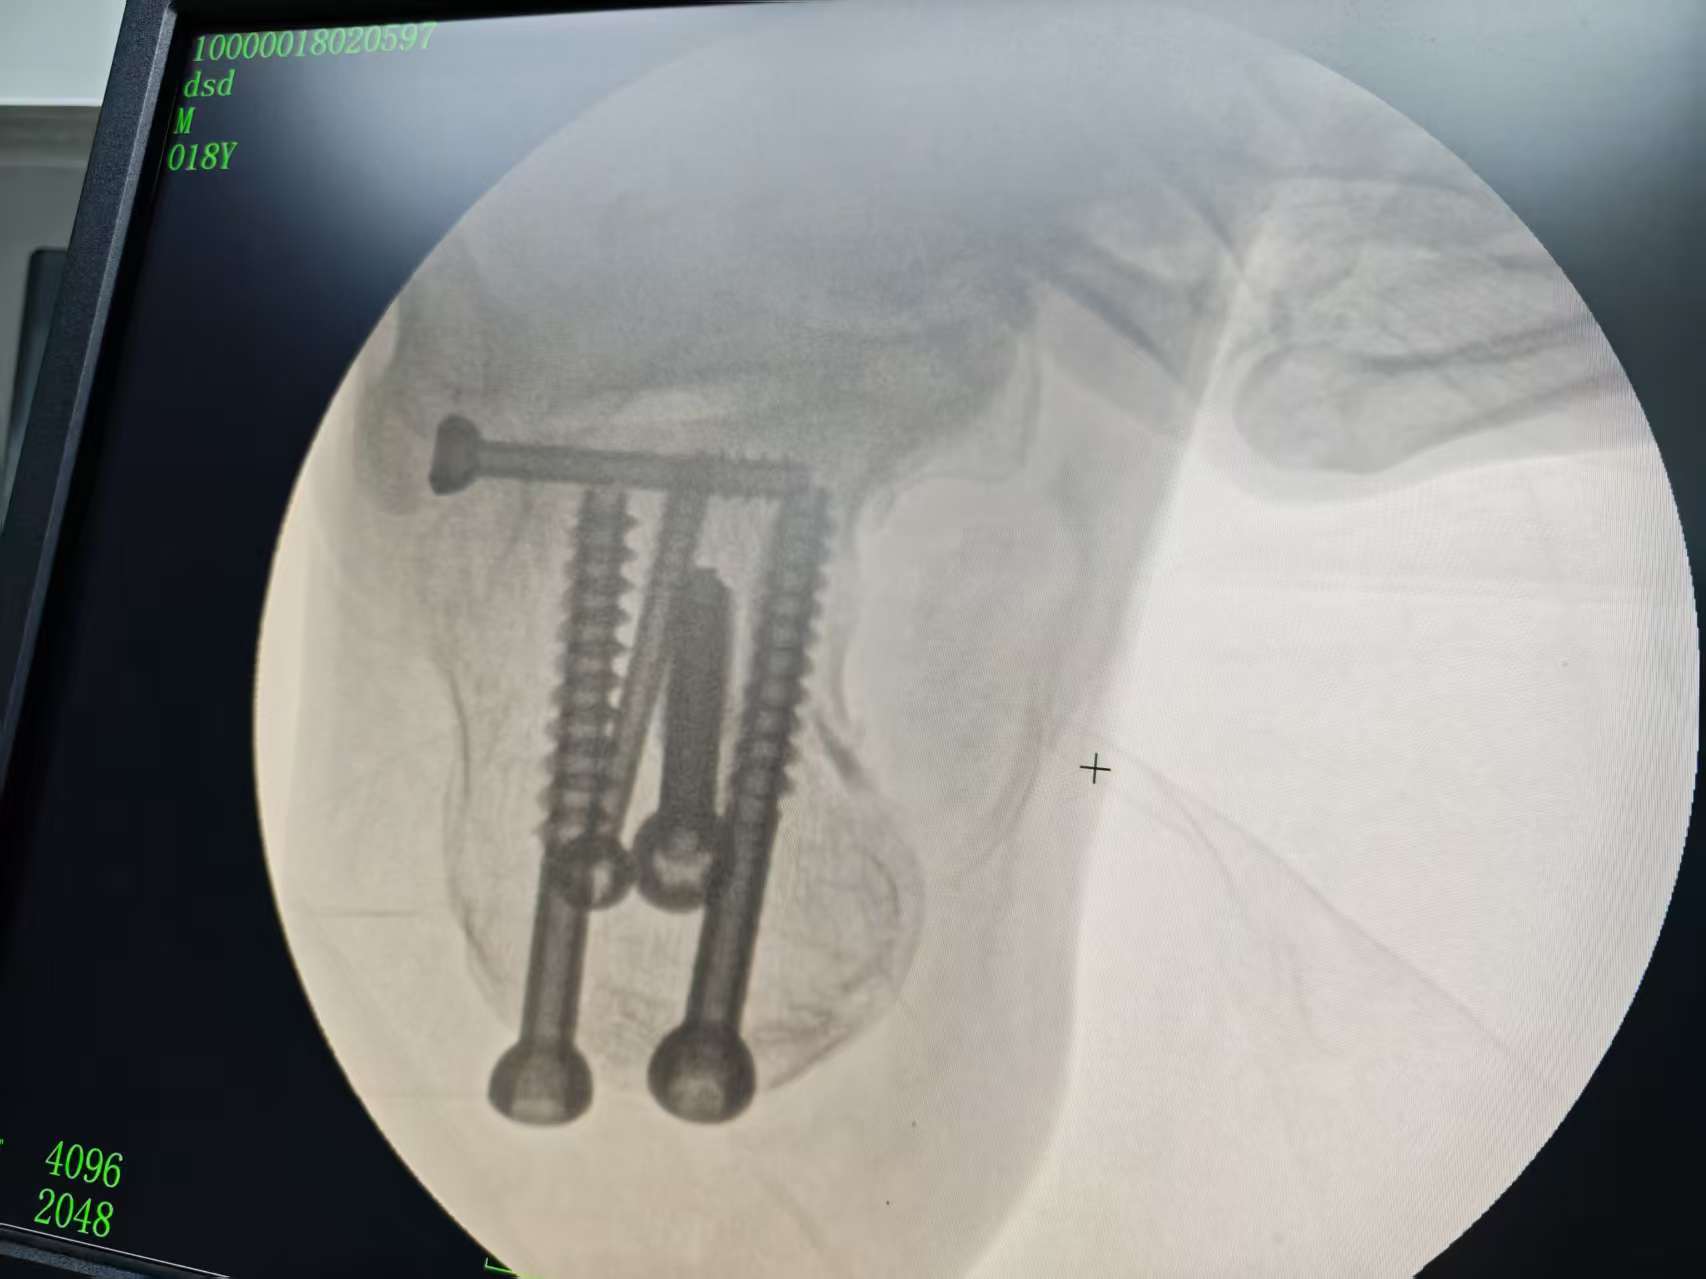

为最大限度减轻患者痛苦、降低并发症风险并促进早期功能康复,湖南医药学院总医院专家,中方县人民医院骨科挂职科主任秦溢主任在充分评估患者伤情后,决定采用创伤更小、技术要求更高的“闭合复位微创内固定术”。术中,在C型臂X光机的实时精准引导下,秦溢通过5个微小的皮肤切口,利用撬拨、牵拉、挤压等手法将骨折块进行微创复位,恢复关节面的平整性及跟骨的高度,长度和宽度,并经皮置入螺钉坚强固定骨折端。整台手术过程顺利,出血量仅5毫升。

术后患者生命体征平稳,足跟部肿胀明显减轻,疼痛感显著缓解。由于手术创伤小,患者第二天即可在医生指导下进行足踝部的非负重功能锻炼,极大地缩短了卧床时间,加速了康复进程。患者及家属对手术效果和医院的精心治疗护理表示非常满意。